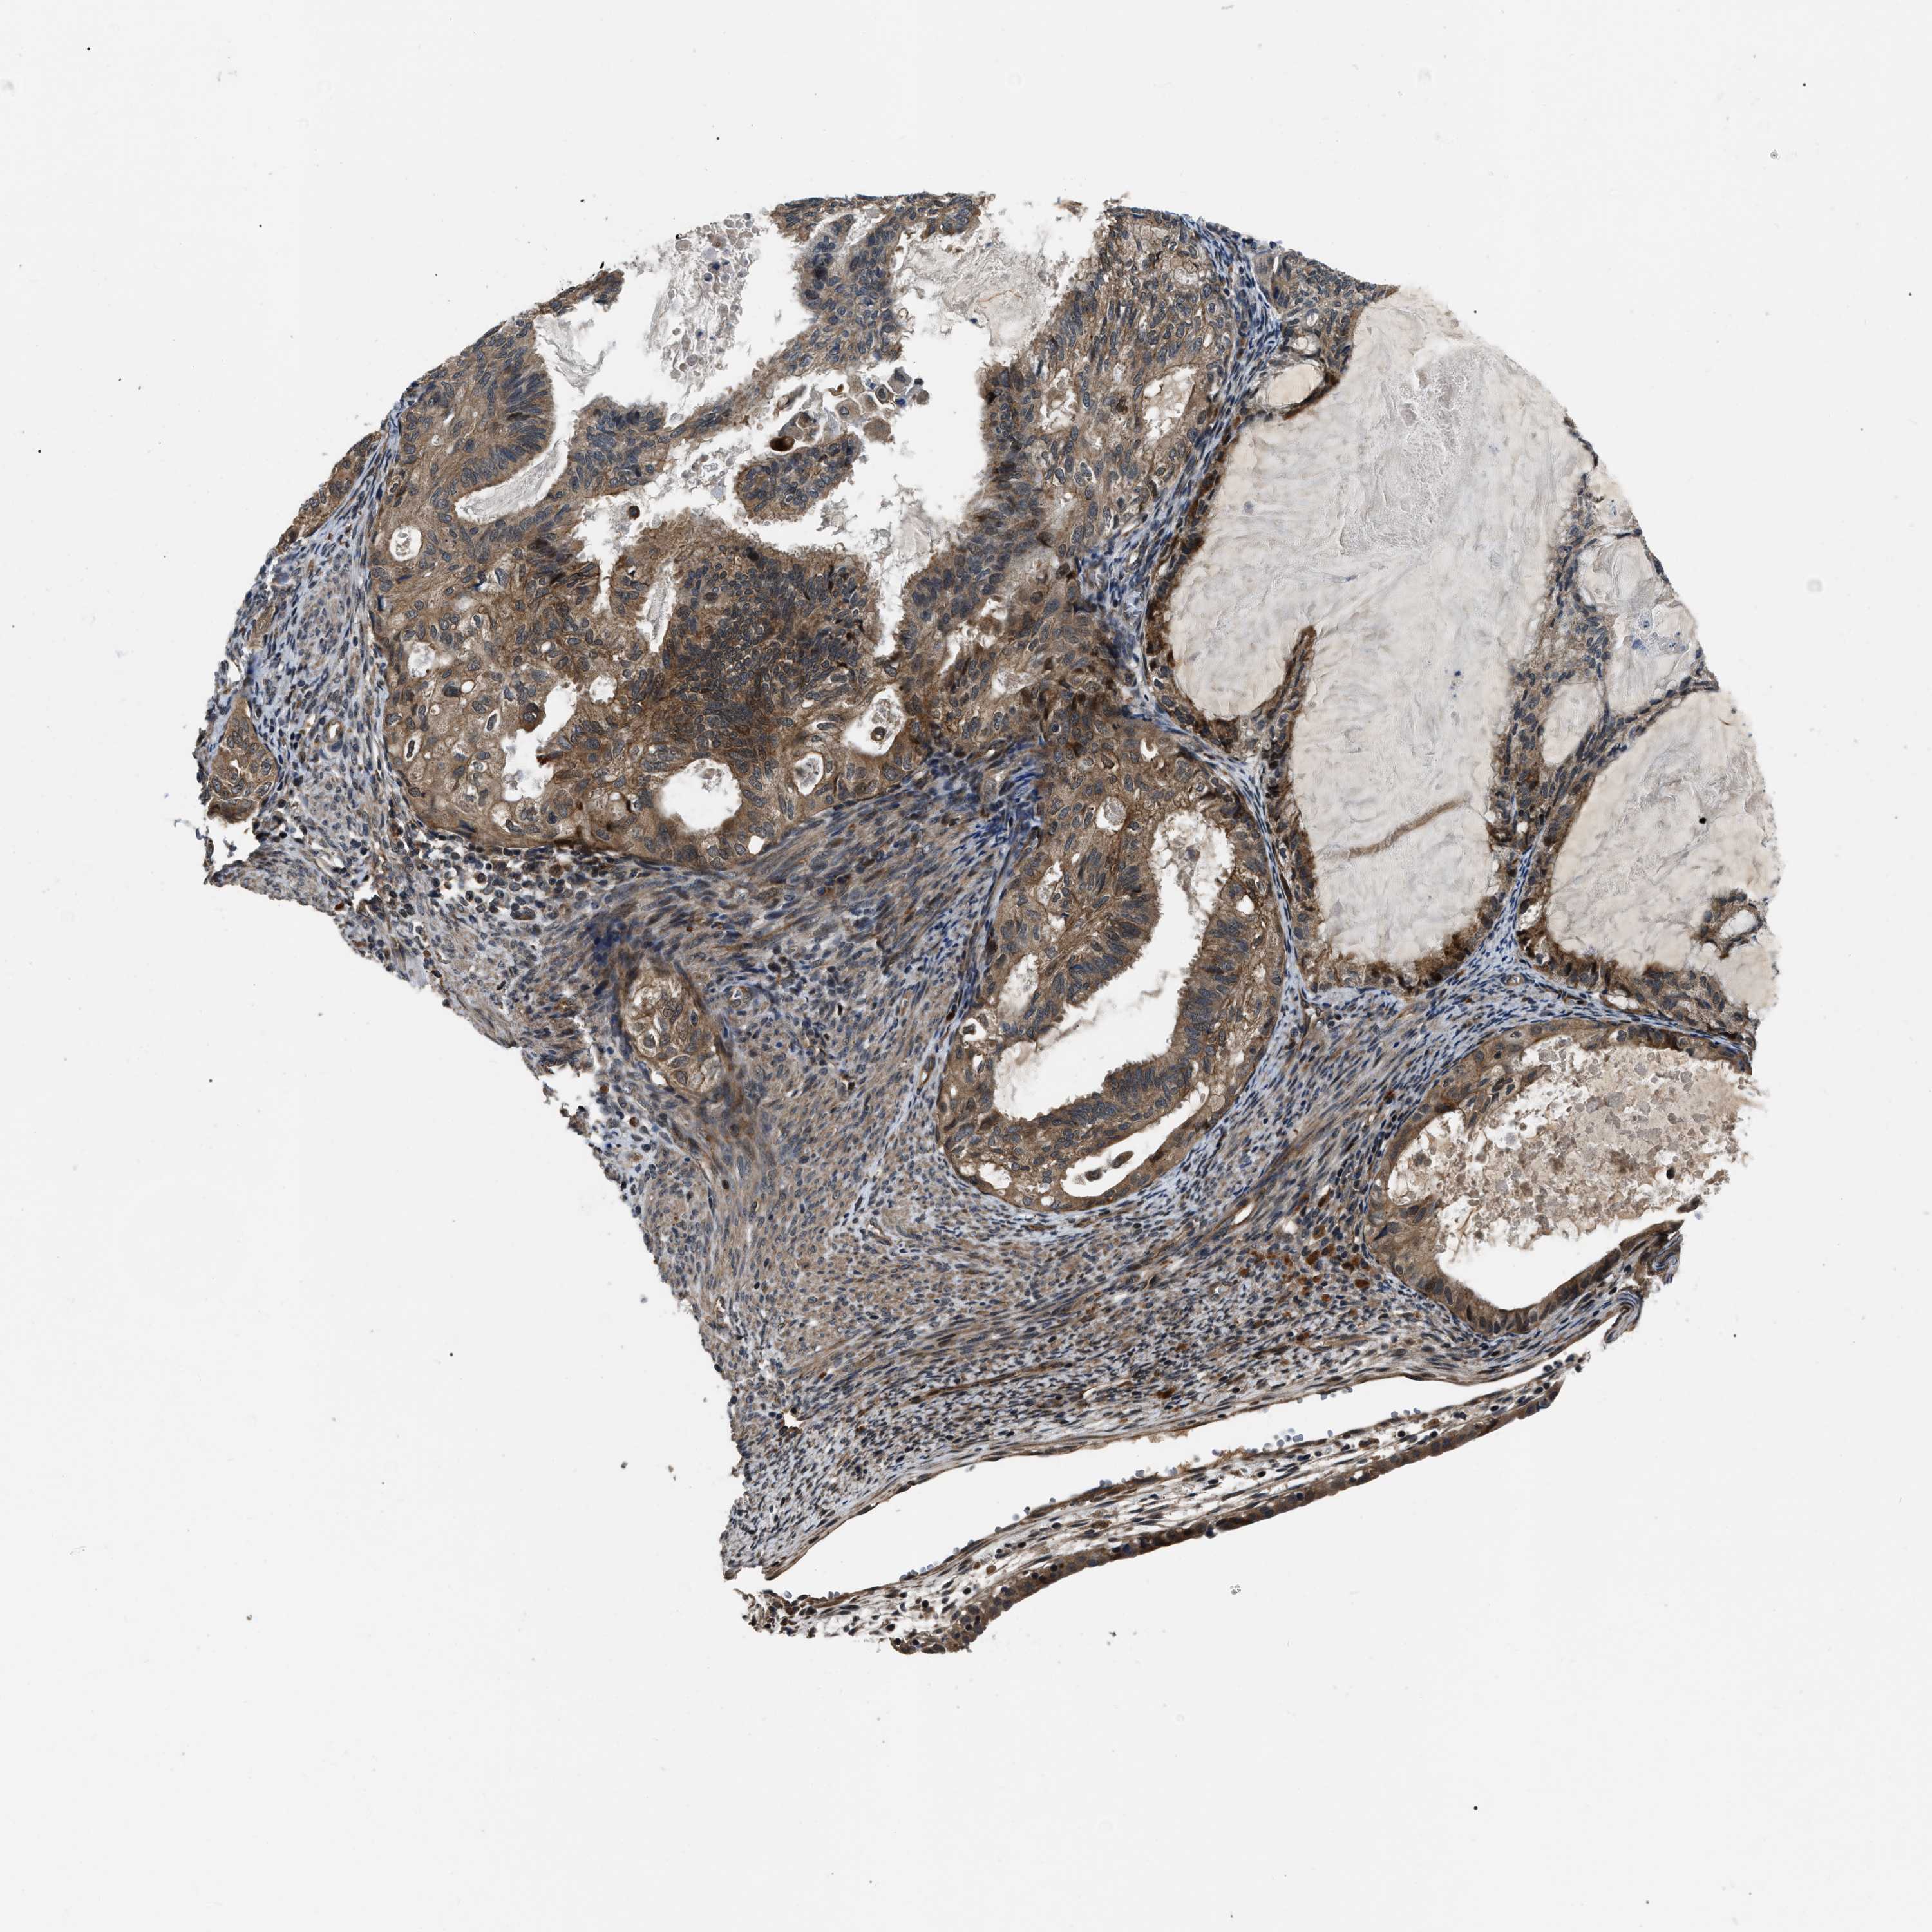

CERVICAL CANCER - Protein expressioni

A mouse-over function shows sample information and annotation data. Click on an image to view it in a full screen mode. Samples can be filtered based on level of antibody staining by selecting one or several of the following categories: high, medium, low and not detected. The assay and annotation is described here.

Note that samples used for immunohistochemistry by the Human Protein Atlas do not correspond to samples in the TCGA dataset.

Antibody stainingi

Antibody staining in the annotated cell types in the current human tissue is reported as not detected, low, medium, or high, based on conventional immunohistochemistry profiling in selected tissues. This score is based on the combination of the staining intensity and fraction of stained cells.

Each image is clickable and will lead to virtual microscopy that enables deeper exploration of all samples and also displays staining intensity scores, fraction scores and subcellular localization as well as patient and tissue information for each sample.

Antibody HPA019353

Antibody HPA019360

Staining

High

Medium

Low

Not detected

Intensity

Strong

Moderate

Weak

Negative

Quantity

>75%

75%-25%

<25%

None

Location

Nuclear

Cytoplasmic/membranous

Cytoplasmic/membranous,nuclear

Squamous cell carcinoma, NOS

Adenocarcinoma, NOS